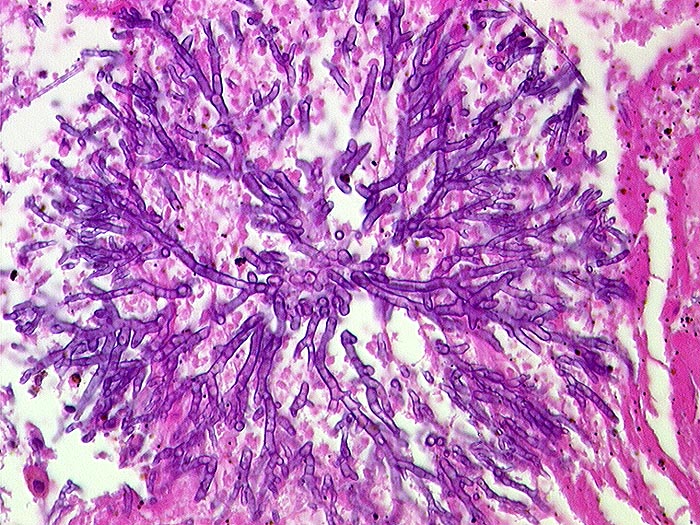

PathoPic ID 547 - Aspergillose

Aspergillose

Entzündung infektiös

Spitzwinklig verzweigte septierte Hyphen.

Histologie